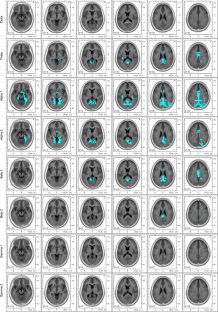

Psilocybin decreased the current source density of neuronal oscillations at 1.5–20 Hz within a neural network comprising the anterior and posterior cingulate cortices and the parahippocampal regions. Most intriguingly, the intensity levels of psilocybin-induced spiritual experience and insightfulness correlated with the lagged phase synchronization of delta oscillations (1.5–4 Hz) between the retrosplenial cortex, the parahippocampus, and the lateral orbitofrontal area.